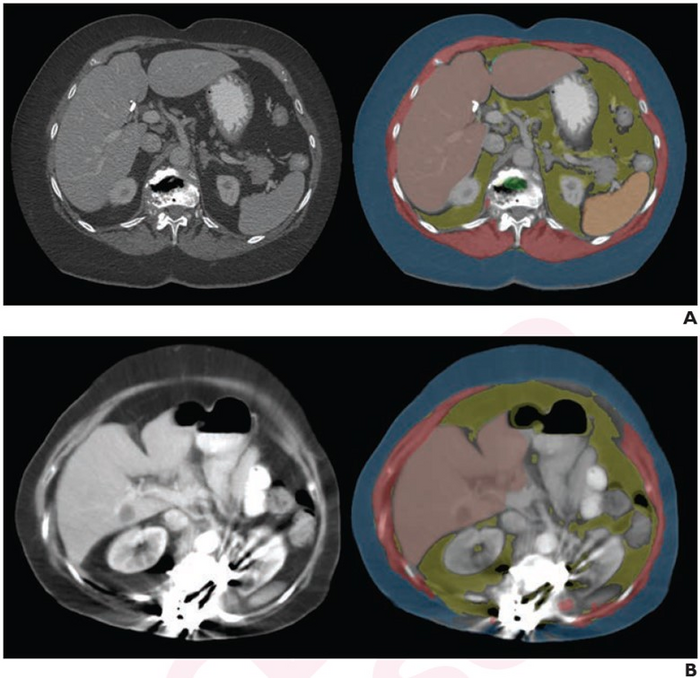

This AJR accepted manuscript included 8,949 patients (mean age, 55.5 years; 4,256 men, 4,693 women) who underwent abdominal CT—performed at different institutions on different scanners from different manufacturers—subsequently transferred to the local PACS for clinical purposes. Deploying three independent automated AI tools to assess body composition via bone attenuation, muscle amount and attenuation, as well as visceral and subcutaneous fat amounts, one axial series per examination was evaluated.

Ultimately, three fully automated AI tools for measuring body composition (vertebral bone, body wall musculature, and visceral and subcutaneous abdominal fat) had technical adequacy rates of 97.8%- 99.1% on Pooler et al.’s sample of 11,699 external abdominal CT examinations—performed at 777 different external institutions using 82 different scanner models from 6 different manufacturers.